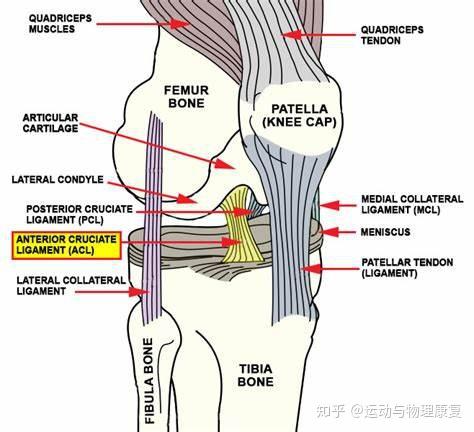

Acl 術後-靭帯再建術後 靭帯再建術後 ハムストリングスを用いて 作成した再建靭帯 手術直前 皮膚切開部のマーク 前十字靭帯が付着していた脛骨と 大腿骨の部分に直径5~9mmの 孔をあけて、その孔へ再建靭帯を 誘導した後、適切な緊張具合で靭 帯を固定します。以上より、acl再建術後では下肢アライメントとの関 係、pcl再建術後では膝屈曲運動との関係を主なキー ワードとして、再建靭帯に加わる牽引負荷を可及的に回 避してリハビリテーションが展開されているように思わ れる。

前十字靭帯損の治療と手術である前十靭帯再建術(Anterior Cruciate Ligament Reconstruction;ACLR)について詳しく説明しています.高知県の川田整形外科ではスポーツなどで損傷した前十字靭帯対して解剖学的二重束再建術を実施しています.前十字靭帯損傷はバスケットボールやバレーボールなどの acl再 建術後のリハビリテーションにあたって は, 少なくとも腱と骨の結合部に関しては術後4 週までは移植腱に過度の負荷を与えないように制 限を設けることが必要と考えられる acl再 建術後のリハビリテーションに 関する生体工学的研究 1術後5ヶ月~8ヶ月:元のスポーツに完全復帰。 鏡視下前十字靭帯(acl)再建術(入院~手術~退院の流れ) acl(膝前十字靭帯再建術)入院案内(pdf) 術後のリハビリテーションのポイントは? 膝の可動域を正常化すること。

膝前十字靱帯 (ACL)損傷とは 膝には、関節の動きをコントロールする4本の靱帯があります。 前十字靭帯はそのうちの一つで、膝が伸びすぎないように抑えたり、膝の前ずれや捻りの方向への動きを制御をしています。 ジャンプの着地や急な方向転換、相手Acl術後の固有感覚の回復過程について,術後6か月で 正常な機能に戻るという報告がある4).今回の総軌跡長の 変化では,男女とも経時的に有意な減少を認め,術後6か 月以降に安定する傾向を示し,同様の結果が得られたと考 acl再建術後患者のスポーツ復帰において、テーピング、装具または両方の併用、いずれが推奨されるか? 確認 7 acl再建術後のスポーツ復帰基準において筋力、関節可動域、動作いずれが判断材料として推奨されるか? 確認 8